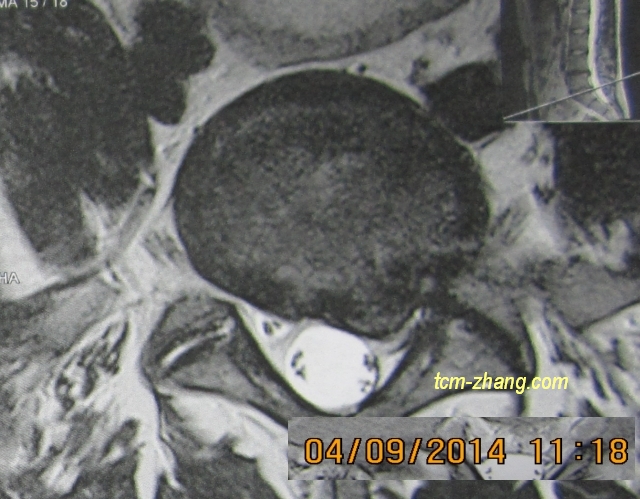

我儿子在2014年7月椎间盘突出,他的骨科医生们确定为只能手术治疗。尽管他的巨大痛苦和效果微乎其微的各种治疗,在他这个年龄(24)我们无法接受这个(手术治疗的)诊断。